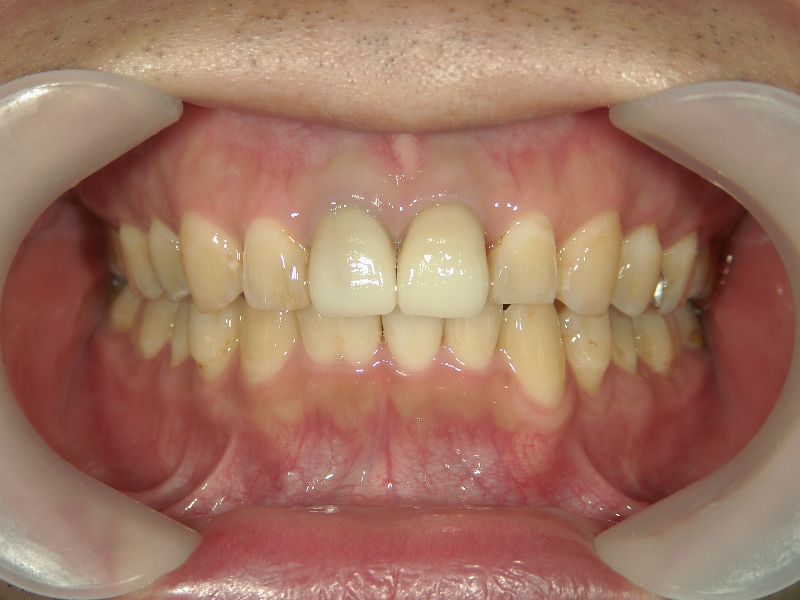

矯正歯科 治療後矯正歯科 全顎ワイヤー矯正 治療後矯正歯科(全顎ワイヤー矯正)治療後

矯正歯科 治療後 E-AMXというセラミックにて左右上1番を被せ直しました。